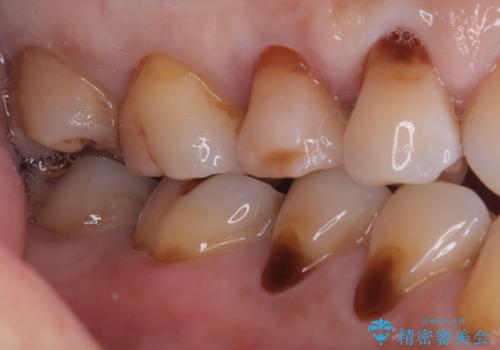

右上5番にう蝕があり、審美性・適合性・材料安定性の高いセラミックインレーでのやり替えとなりました。

右上5番の近遠心にう蝕が認められたため、CR裏層の後MOD窩洞のセラミックインレーとしました。

インレーセット時はラバーダム防湿を行っています。